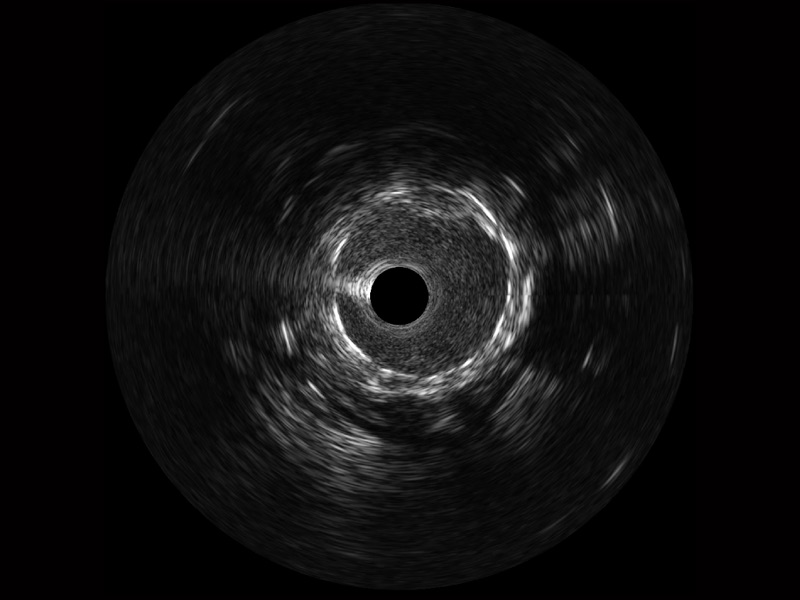

• 球速体育入口宽频IVUS图像

• 传统IVUS图像

对比传统IVUS导管成像,球速体育入口宽频IVUS图像的近场支架梁显影更细腻,远场中膜外血管仍清晰可辨,兼顾远中近,兼顾分辨力与穿透深度